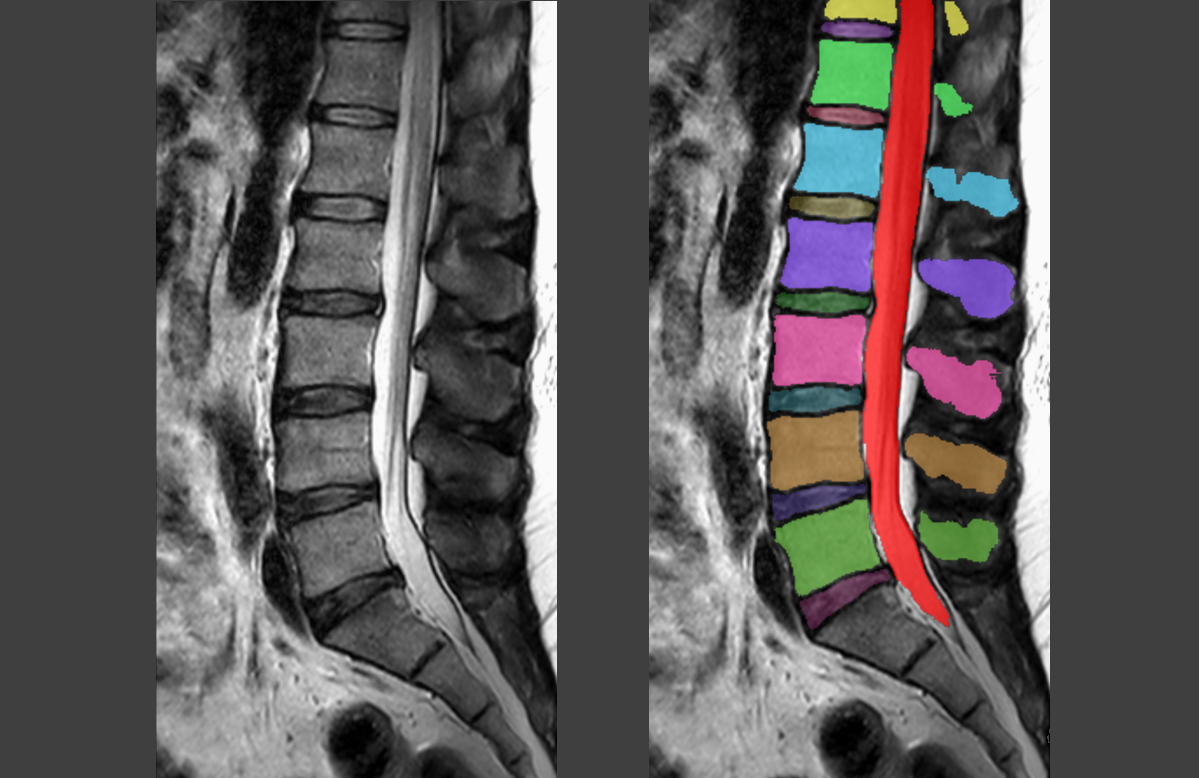

Om dat te testen trainde Van der Graaf eerst een computer om op MRI-scans de structuren in de wervelkolom te herkennen. ‘We voerden bijna vijfhonderd scans in uit vier ziekenhuizen, waarvan we alle structuren helemaal met de hand hadden ingekleurd. Zo leerde de AI hoe de rug eruitziet, en kon het algoritme vervolgens ook zelf de onderdelen inkleuren en eventuele afwijkingen opsporen.’